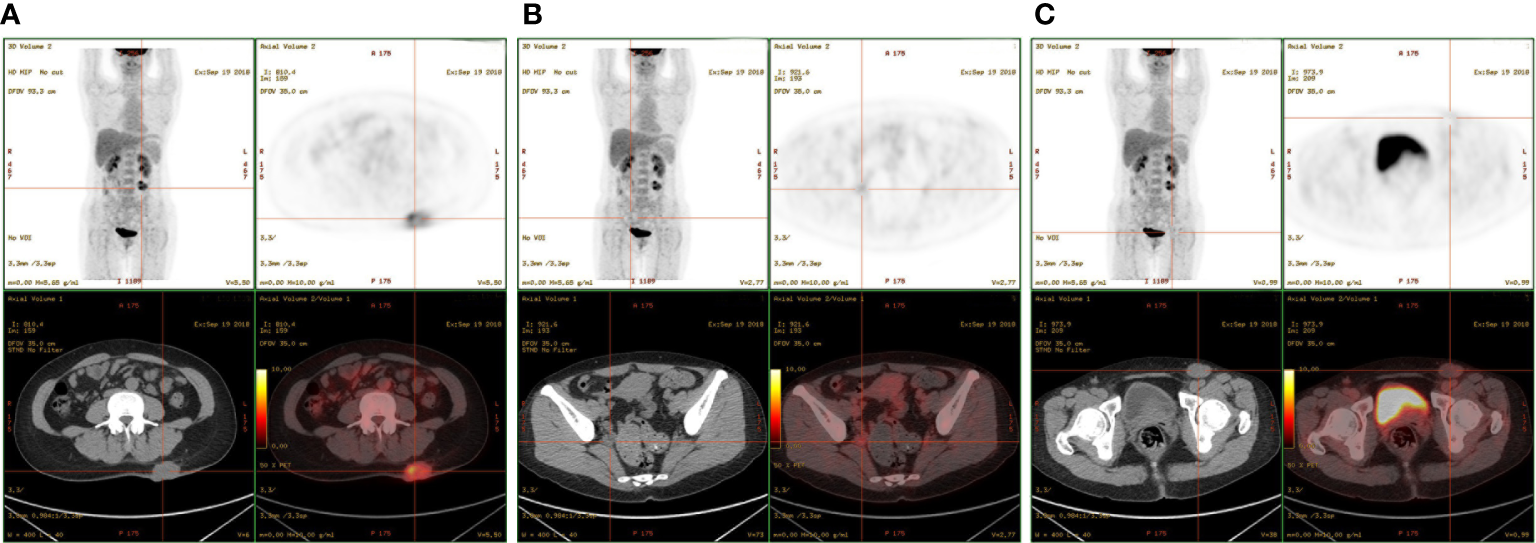

The patient had no previous medical history and no notable personal and family history. Physical examination revealed a palpable mass of about 4 × 2 cm in the left lower back and enlarged lymph nodes in the left groin. Laboratory tests showed that the complete blood count and blood biochemical indicators were basically within the normal range. A positron emission tomography/computed tomography (PET/CT) scan was done on 21 September 2018, and it revealed a malignant tumor that was located on the left lower back with right pelvic wall and bilateral inguinal lymph node metastasis (Figures 1A-C). Surgery was performed to remove the lesion on the left lower back on 25 September 2018 with a tumor-free margin. Pathological inspections confirmed the diagnosis of SGC, and immunohistochemistry results indicated that the mass was CK7+, P63+, CK5/6+, CK14+partial, GCDFP-15−, GATA-3−, p40−, and Ki-67 10% (Figures 2A-F). Her magnetic resonance (MR) scanning image on 12 October 2018 showed that the number of lymph nodes increased in the bilateral inguinal region, and the left one was enlarged, suggestive of malignant disease (Figure 3A). Because the left lesions were surgically unresectable, the patient agreed to undergo a cytotoxic chemotherapy regimen consisting of docetaxel and nedaplatin every 3 weeks for seven cycles. MRI revealed stabilization of the disease (Figure 3B). Then, she received intensity-modulated radiation therapy (IMRT) with 60 Gy to the gross tumor volume (GTV) and 50 Gy to the clinical tumor volume (CTV). After the radiotherapy, the patient was reviewed regularly, and the tumor size was obviously reduced (Figure 3C). However, MR scanning on 4 December 2019 revealed that the inguinal lymph nodes became larger (Figure 3D). We recommended that she undergo whole-genome sequencing. Due to the high price and limited specimen, only peripheral blood was used to detect PD-L1 expression. PD-L1 expression was 10%. Then, she underwent a chemotherapy and immunotherapy regimen consisting of albumin-bound paclitaxel and camrelizumab (a PD-1 inhibitor) for eight cycles. During the treatment, MRI showed stabilization of the disease (Figure 3E). On 14 December 2020, MR scanning showed that the number and size of the inguinal lymph nodes increased and were larger than the previous ones (Figures 3F, G). We repeatedly communicated with the patient about the treatment plan and told her that the prognosis was not good, but the patient still agreed to continue the treatment. Then, the patient underwent chemotherapy and immunotherapy with pemetrexed, nedaplatin, and camrelizumab for eight cycles. However, the inguinal lymph nodes were poorly controlled and growing larger according to the MRI result (Figure 3H). Then, the patient refused further treatment and went back home. Through telephone follow-up, we learned that the tumors in the left groin continued to grow and were ulcerating. The patient gradually developed pleural fluid and ascites. She died on 2 September 2021. To date, the survival time of this patient is 35 months. The timeline for treatments and efficacy evaluations in this case is summarized in Figure 4.

Figure 1

PET-CT showed multiple masses located in the (A) left lower back, (B) right pelvic wall, and (C) inguinal region.